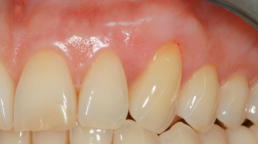

Mikrochirurgischer Wundverschluss

Gingivatransplantat fixiert

Zustand 3 Wochen post OP